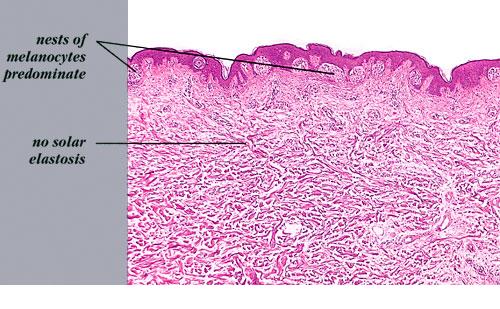

Read MoreJunctional melanocytic naevus= الوحمة ميلانية الخلايا الوصلية